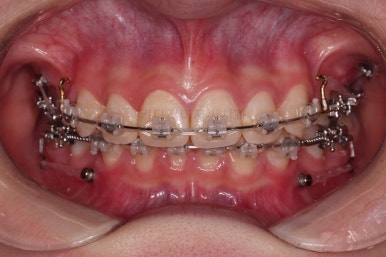

교합이 잘 맞아졌고요.

위아래 앞니도 서로 가까워졌어요.

치열도 가지런해졌고, 과개교합도 잘 개선이 되었습니다.

연산동치아교정 이제 전후 사진을 비교해 볼게요.

아래 앞니가 2개인 것이 표시가 안날 정도로 자연스럽게 교합이 맞아졌습니다.

얼굴모습에서도 발치교정이지 윗입술이 많이 들어가지 않게끔 아랫니를 최대한 앞으로 빼둔 상태여서 윗ㅇ입술은 양호하며, 아랫입술은 아래쪽에 깊게 패여있던 주름도 많이 퍼졌습니다.

여러 가지 제약이 많았던 상황이었지만 많은 부분들이 개선된 만족스러운 연산동치아교정 치료였습니다.

이상 아래 앞니가 2개 선천 결손인 환자분을 임플란트 없이 추가 발치로 교합을 맞춰주었던 연산동치아교정 치료사례였습니다.